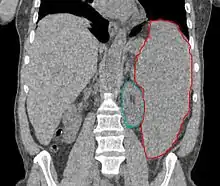

- فحص نخاع العظم. هذا ضروري للتأكد من صحة التشخيص كون نخاع العظم المصاب بخلل التنسّج يعتبر العلامة المميزة لخلل التنسّج النقوي.